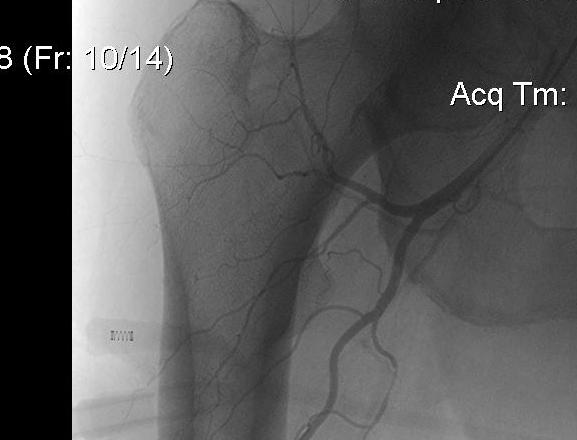

Profunda femoris

Artery to thigh muscles

- exits laterally at termination of femoral sheath

- 3-4 cm distal to inguinal ligament

- arises from lateral side

- passes between pectineus and adductor longus

- runs behind adductor longus

- runs down on adductor brevis and magnus

- gives 4 perforating branches

Lateral circumflex

- lateral side of profunda

- passes laterally between branches of femoral nerve

- under sartorius and rectus